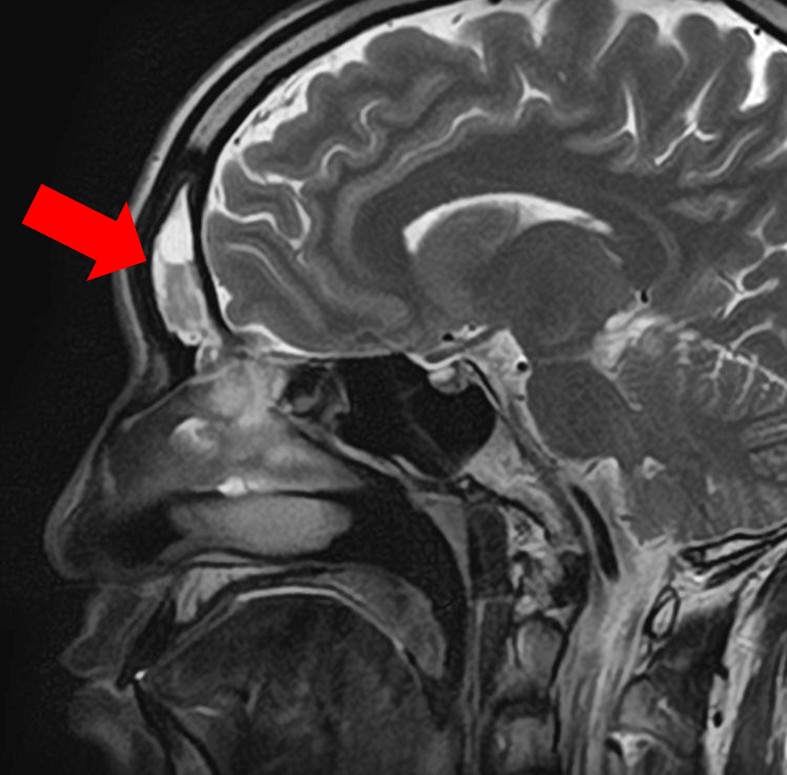

4.【画像解説】MRIでわかる副鼻腔炎と脳の状態

当院では、頭痛の原因を特定するためにMRI検査を実施しています。

正常 副鼻腔 MRI

正常な上顎洞

副鼻腔炎MRI画像

膿がたまっている上顎洞

目の下・周囲の痛みの原因

正常な前頭洞

膿がたまっている前頭同

眉間の痛みの原因

MRI検査の最大のメリットは、「鼻が原因の頭痛」と「脳疾患が原因の頭痛」を一度の検査で同時に、かつ詳細に判別できる点にあります。

【MRIでどこを見るのか】

MRI画像では、脳や脳血管はもちろん、鼻の奥にある空洞を精査します。

健康な状態: 空気が入っているため、炭のように「真っ黒」に映ります。

副鼻腔炎の状態: 膿や粘膜の腫れがある部分は、「白く濁った雲」のように映し出されます。